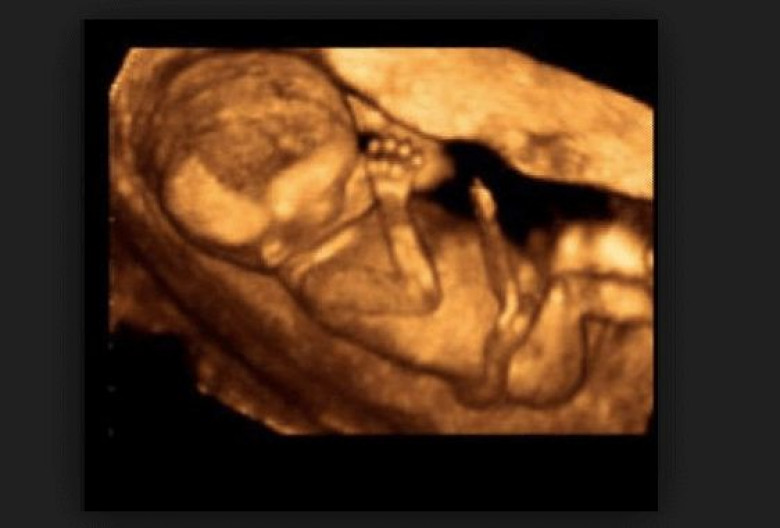

Աղջիկը վճռականորեն մտավ հիվանդասենյակ, որտեղ նրան հետազոտեցին: Հետազոտության արդյունքները սովորաբար կանանց ցույց չեն տալիս, սակայն Ջիլը էկրանին տեսավ իր ներսում զարգացող պտղին:

Երեխան տղա էր, իսկ հետազոտության արդյունքում նա տեսավ նրա ոտքերը, ձեռքերը, անգամ քիթը: Ամենավճռական պահին, երբ պետք է սկսվեր երեխայի հեռացման գործընթացը, Ջիլը պարզապես զգաց, որ պետք է դուրս փախչի այդ հիվանդանոցից: